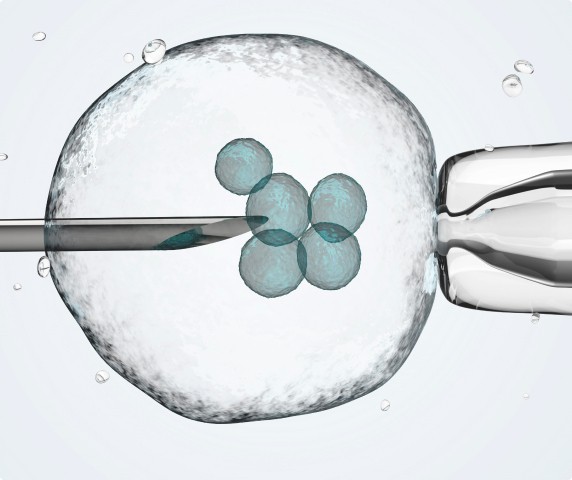

Regenerative Medicine

We prevent disease and regenerate damaged tissue with techniques and mechanisms similar to those the body uses to naturally renew cells.